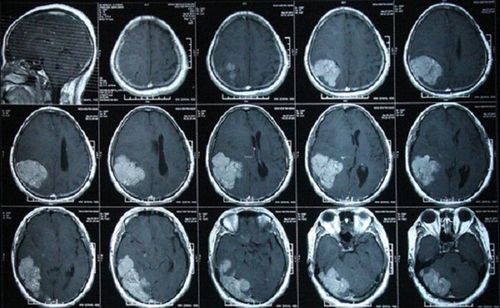

Hình ảnh máu tụ dưới màng cứng trên phim CT sọ não không tiêm thuốc cản quang

Máu tụ dưới màng cứng là tình trạng chảy máu ở các khoang quanh não. Hình ảnh máu tụ dưới màng cứng trên phim CT sọ não không tiêm thuốc cho thấy sự hiện diện và kích thước của khối máu tụ hình thành giữa màng cứng và màng nhện.